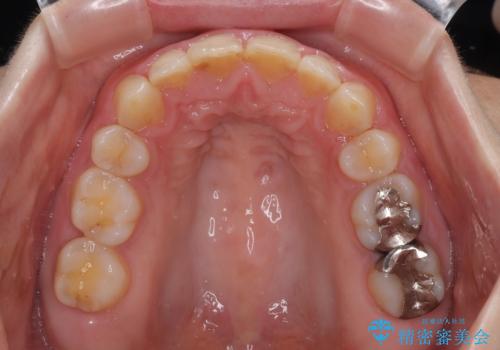

- 上の前歯が出っ歯と突出した口元を気にして来院された患者様です。

上顎歯列全体が前方に飛び出している印象であったので、上顎左右の第一小臼歯2本を抜歯し、ワイヤー装置にて抜歯矯正を行うこととしました。

骨格的に上顎が前方にあり、上顎のみの抜歯矯正のため、期間はかかることが予想されましたが、スムーズに移動してくれたおかげで、2年弱の短期間で終えることができました。